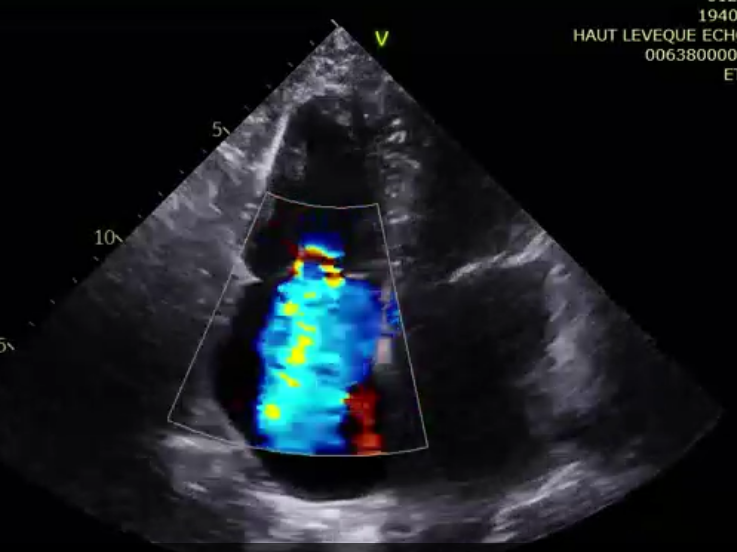

術前超聲提示極大量三尖瓣反流

術后超聲提示微量瓣周漏